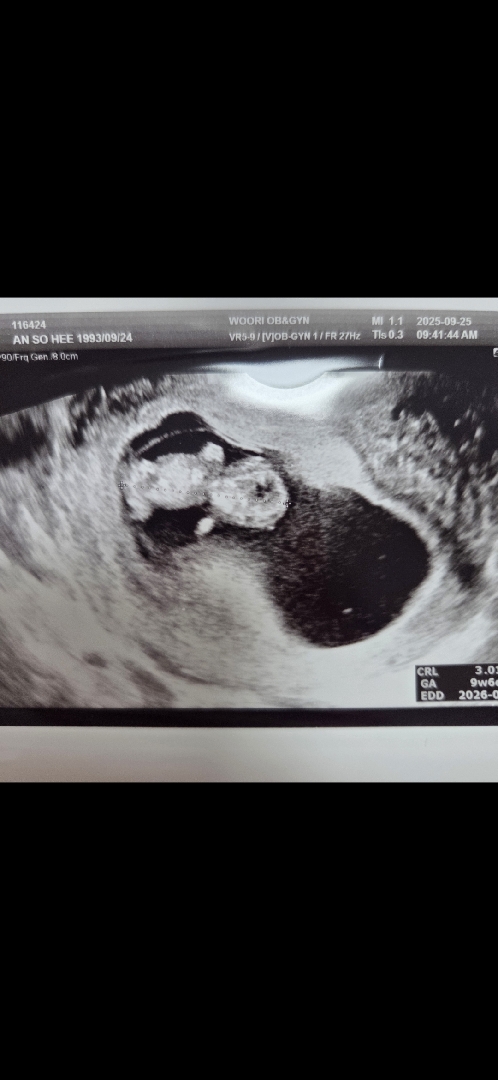

9주6일 젤리곰(?)♥️

컨디션도 안좋고 배도 쿡쿡 쑤셔서 회사에 말하고 병원 갔더니 찰떡이는 아주 잘 꼬물꼬물 거리는중ㅎㅎ 건강해서 다행ㅠㅠㅠㅠ 9주차 컨디션 오락가락 눈물이 쏟아질것 같은 기분 무기력ㅠㅠ다들 이렇죠??ㅎㅎㅎ임신 힘드네여ㅠㅠ